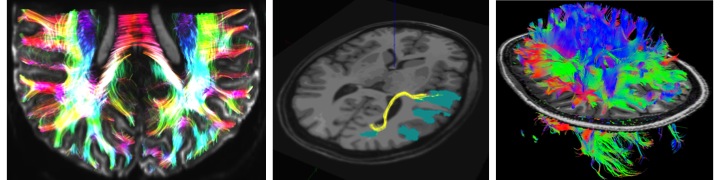

- MR spectroscopy and imaging

- Introduction to MR spectroscopy